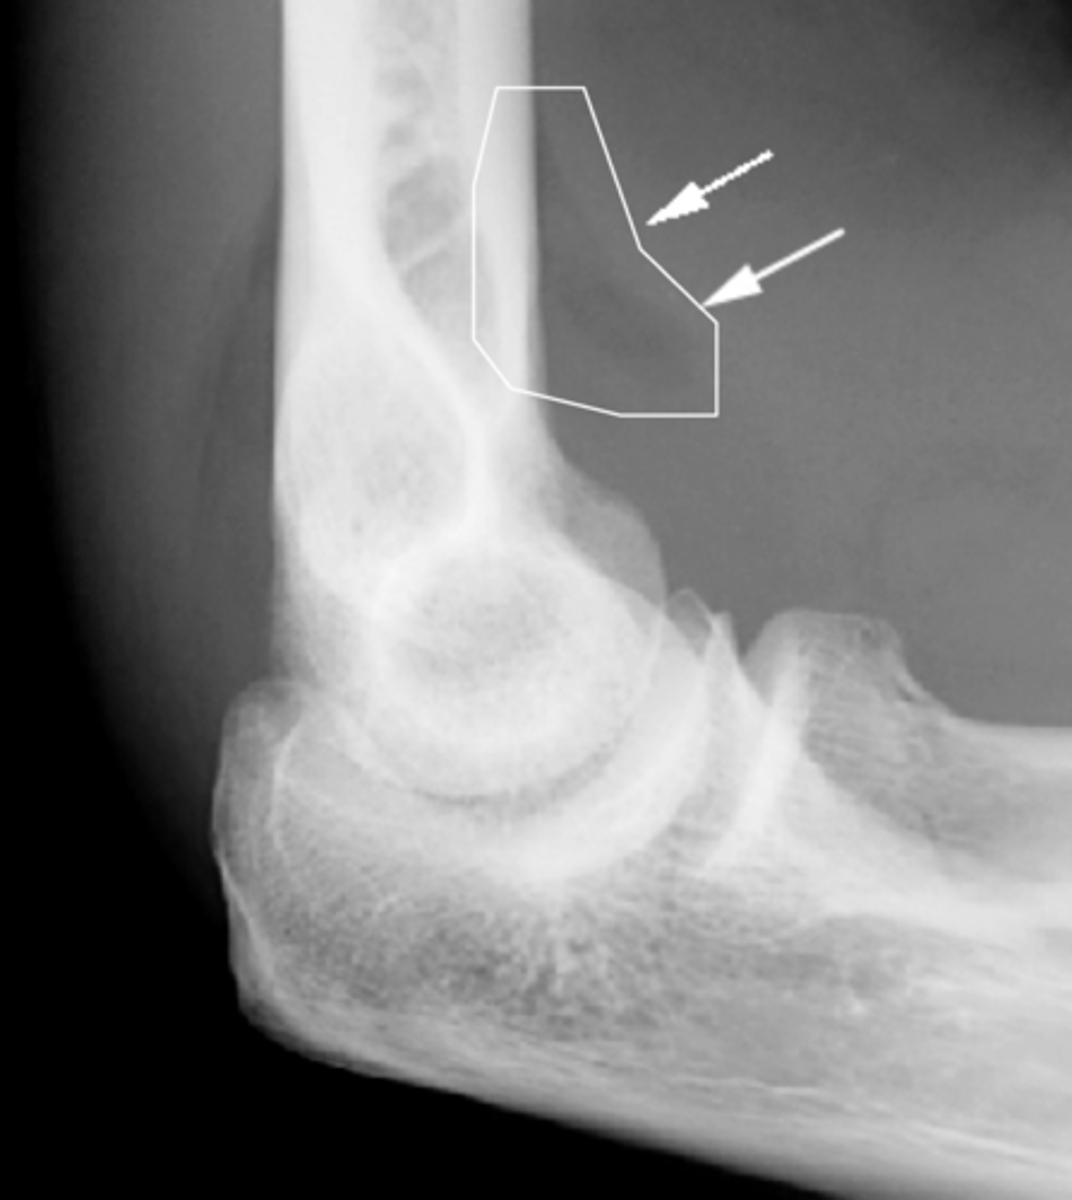

What is a "sail sign"? What is it caused by?

Elevation of a fat pad (ex: when the elbow is injured, it fills up with fluid that pushes the fat pad and lifts it away from the bone itself)

What indicates effusion of a joint capsule on a plain film radiograph?

Radiolucent joint recess due to joint swelling (i.e., effusion) that pushes the proximal superior recess out